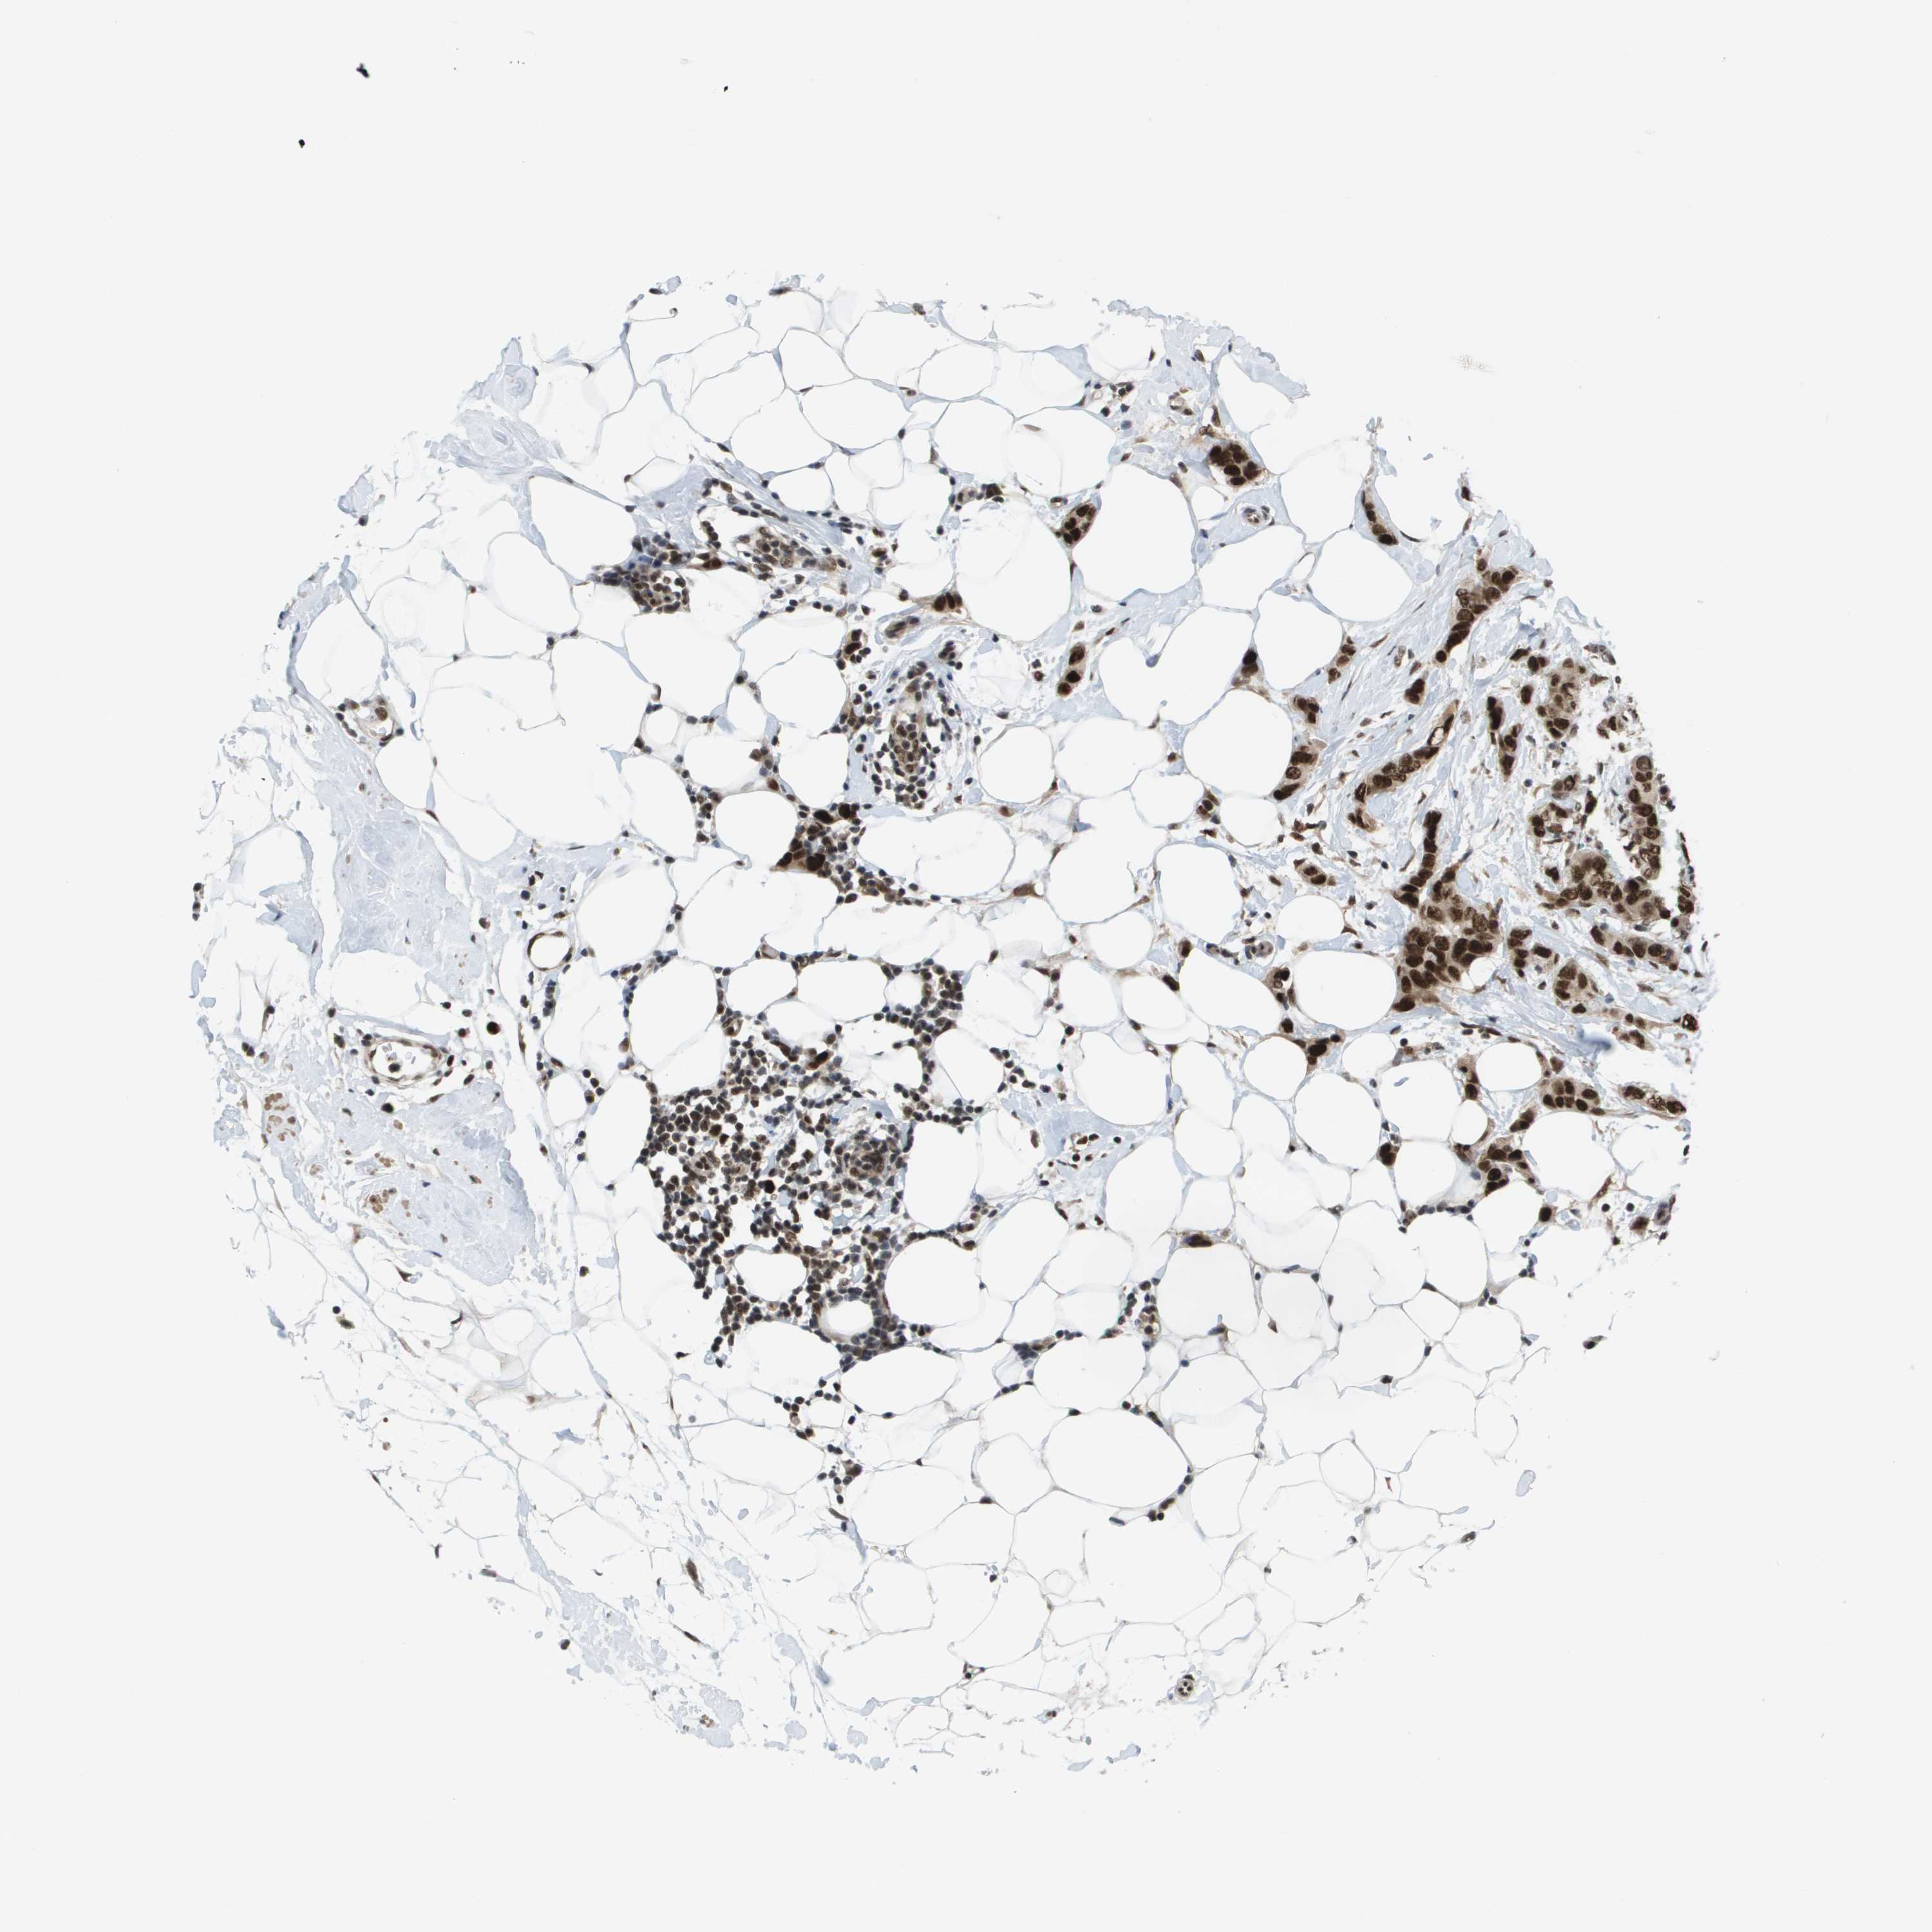

CANCER BREAST CANCER Show tissue menu

BRCA TCGA BRCA VALIDATION PROTEIN EXPRESSION